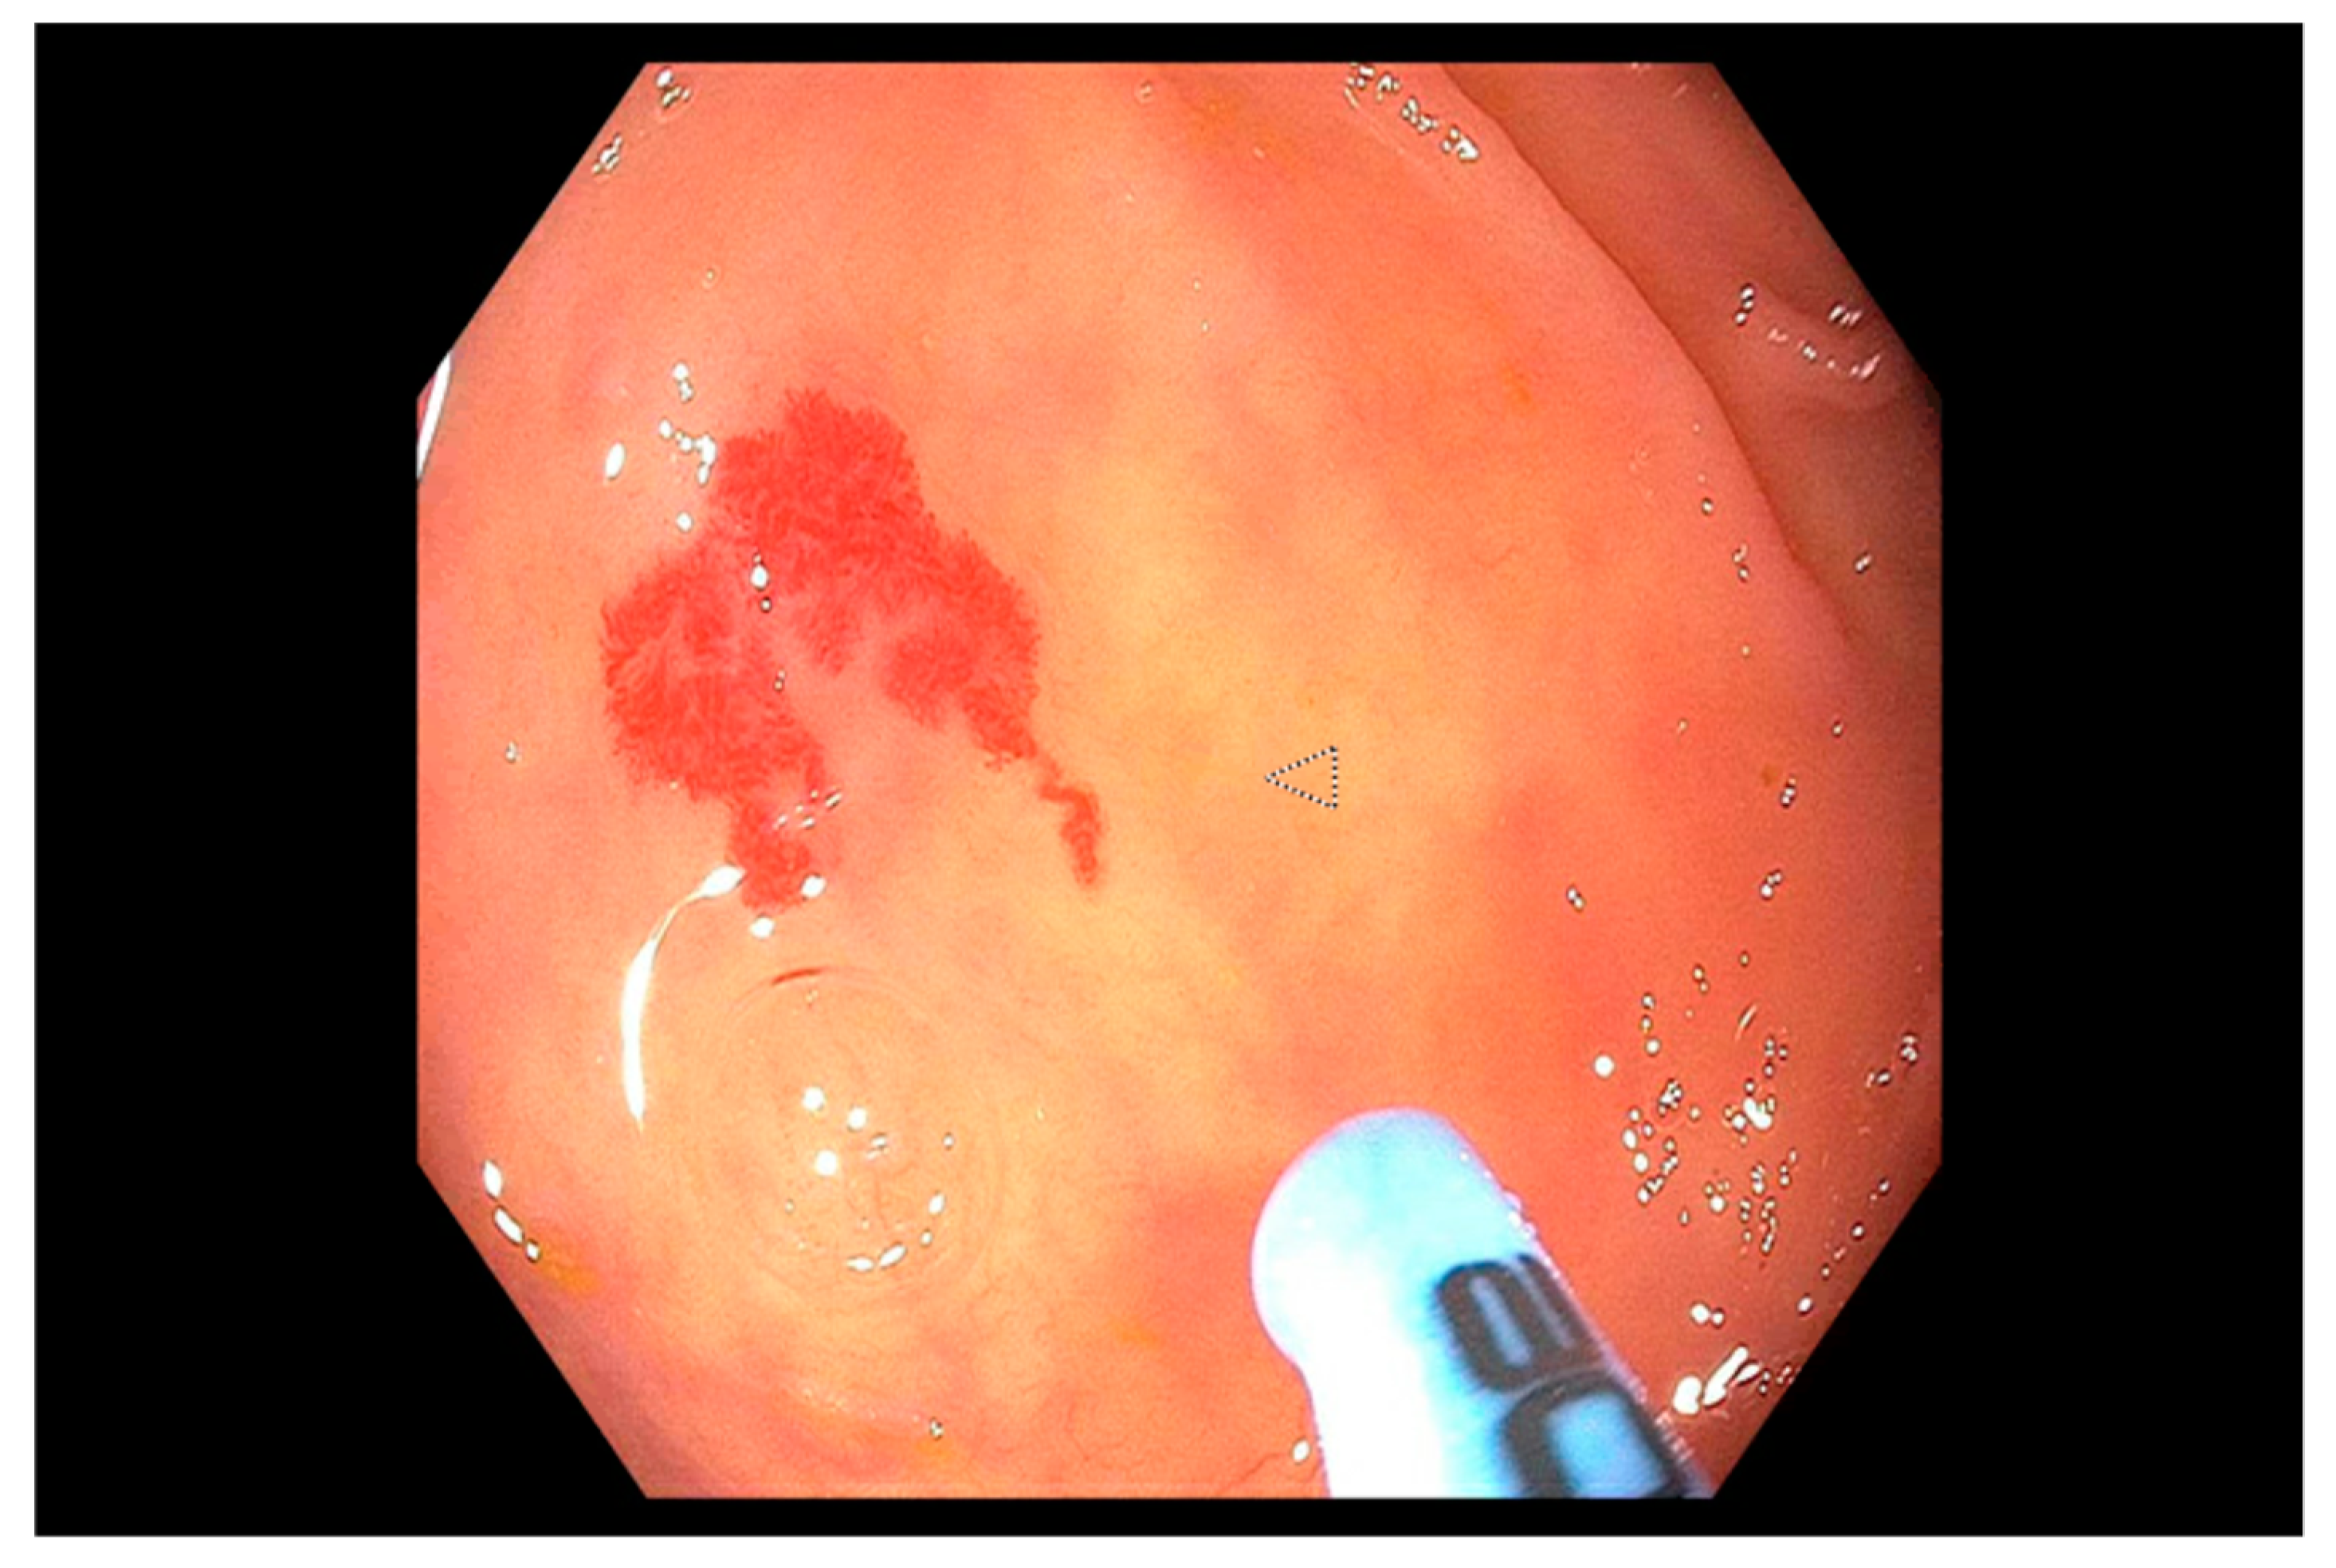

Role of Endoscopy in Lower Gastrointestinal Bleeding